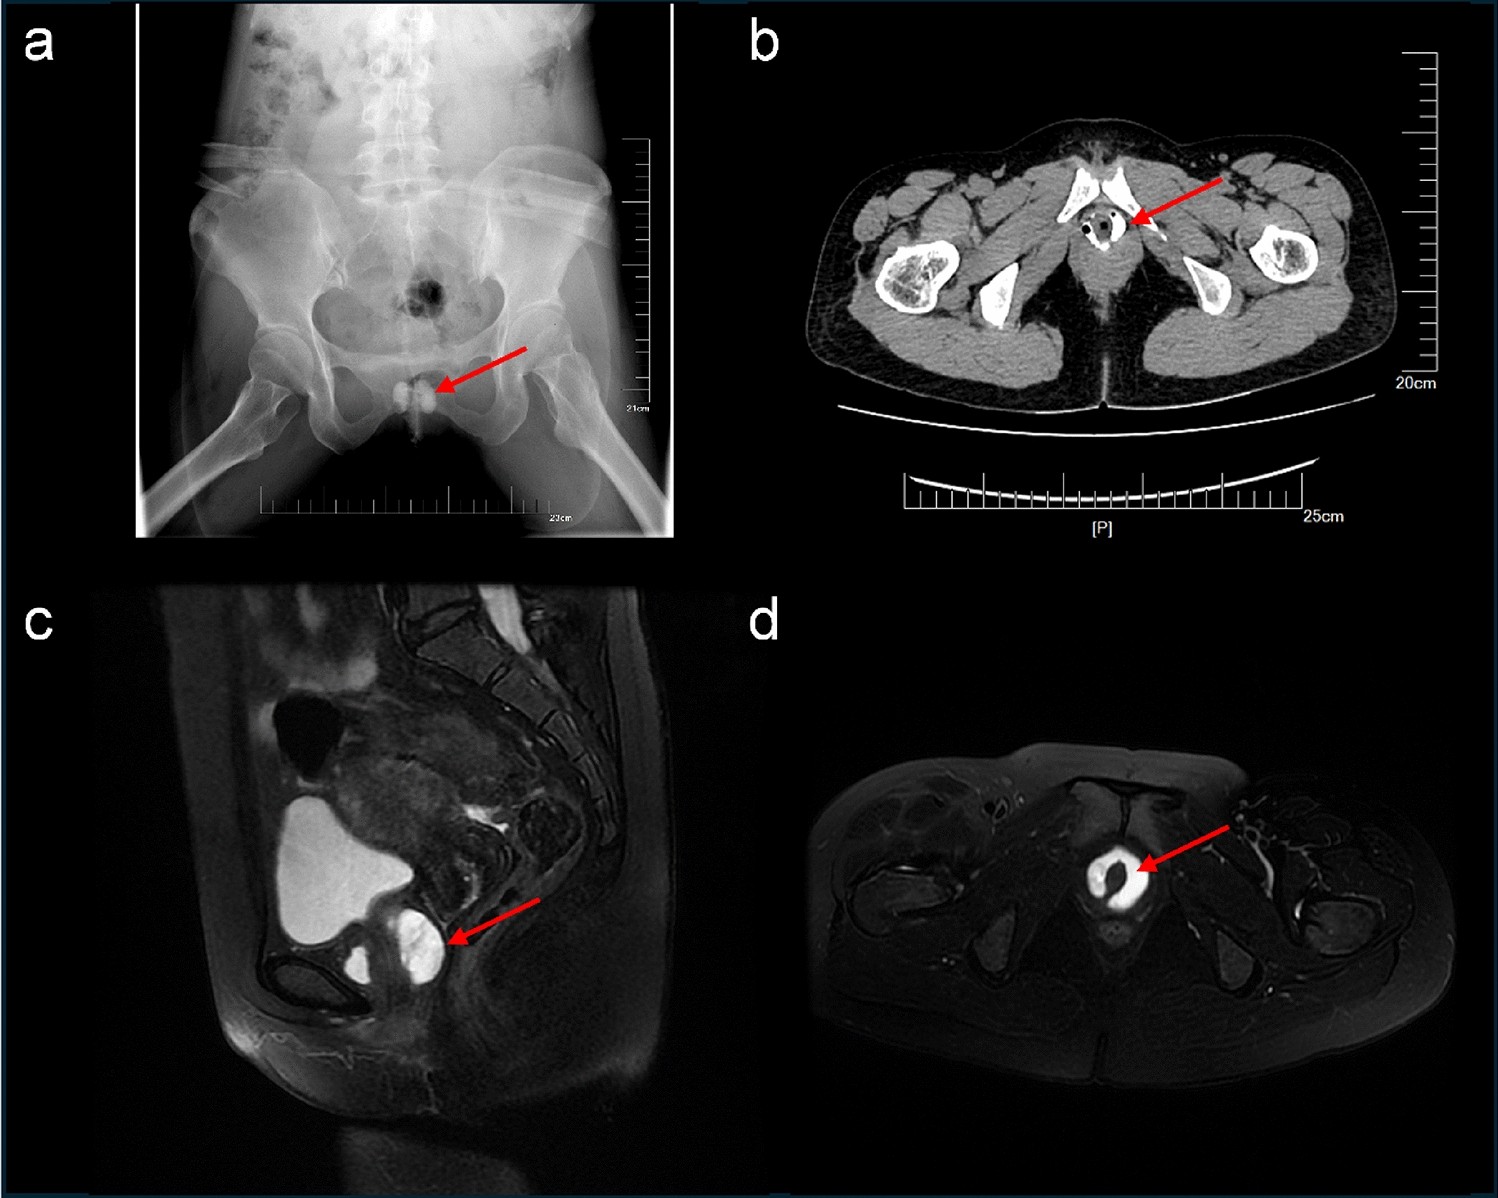

Fig. 1

From: Experience in conversion of symptomatic urethral diverticulum to asymptomatic status through surgery

Representative MR, urethrogram and pelvic CT after urethrography. a Urethrogram of one patient; b Pelvic CT after urethrography showed a horseshoe-shaped UD; c A sagittal MRI T2 weighted image of one patient, UD showed hyperintensity; d A transverse MRI T2 weighted image showed a circumferentially UD. The arrows indicate the urethral diverticula.